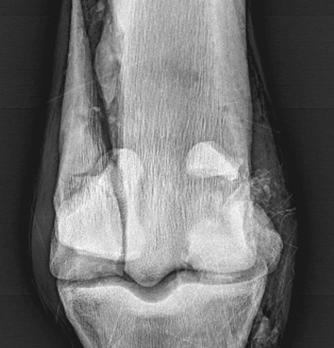

REDUCING THE RISK OF FRACTURES

Preventing serious fractures in the racehorse

Christopher Riggs tells us of the work being done on the prevention of serious fractures in the racehorse.